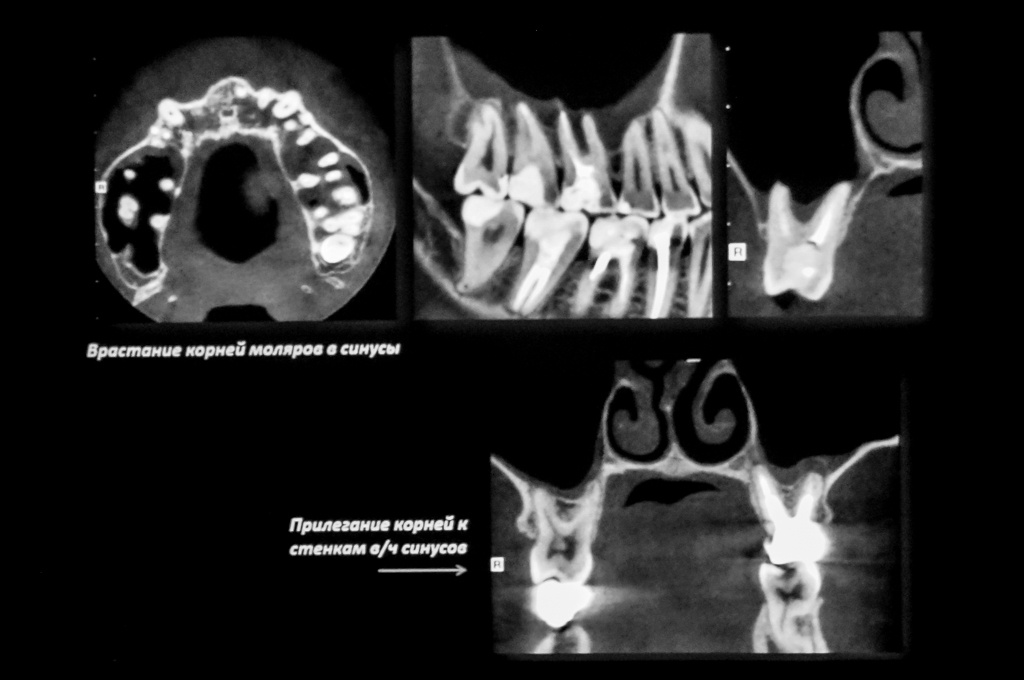

4 ноября 2017 года в г. Москва проходил Курс Лучевая диагностика в стоматологии на основе КЛКТ, как эффективного метода визуализации. Занятия проводил врач-стоматолог НИК Дентал Гуру, ассистент кафедры общей и клинической стоматологии РУДН СЕДОВ Юрий Георгиевич

Курс Лучевая диагностика в стоматологии на основе КЛКТ,  как эффективного метода визуализации